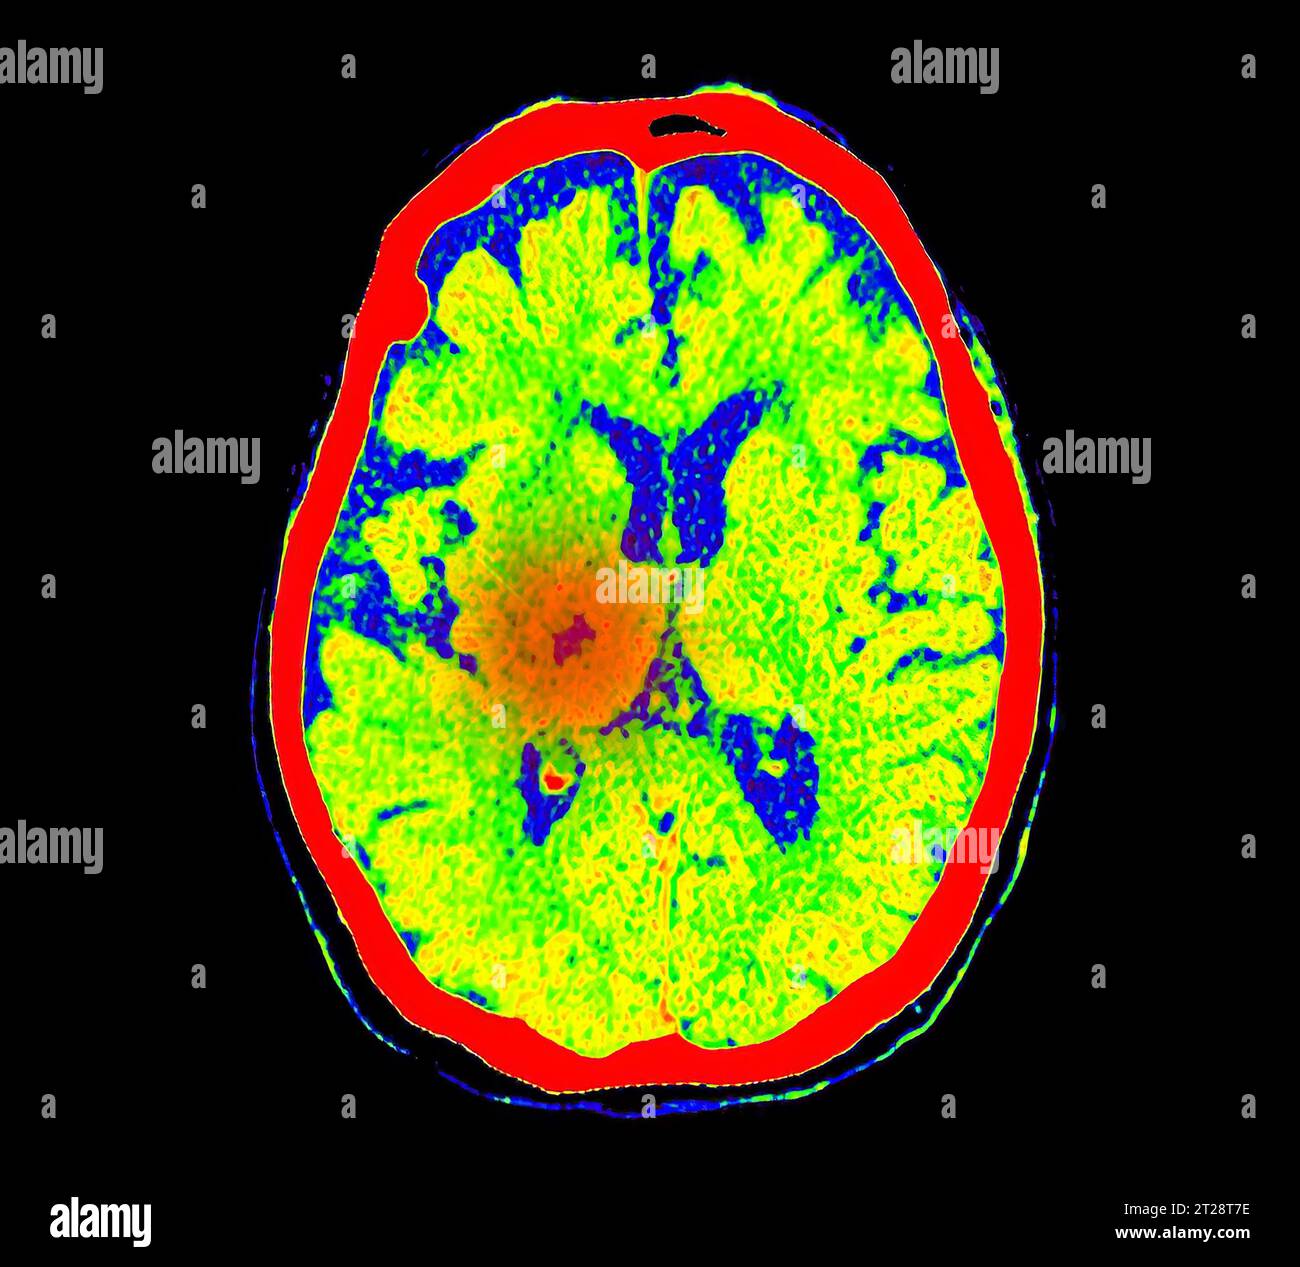

From www.alamy.com

CT Brain Perfusion or CT scan image of the brain axial view showing How Do I Know If I Need A Brain Scan Brain damage, a stroke or Major structural changes, such as pressure from a tumor pushing on one side of the brain can be detected with a brain ct scan. It enables clinicians to focus on various parts of the brain. An mri of the brain can be used to evaluate many symptoms which may be caused by abnormalities in the. How Do I Know If I Need A Brain Scan.